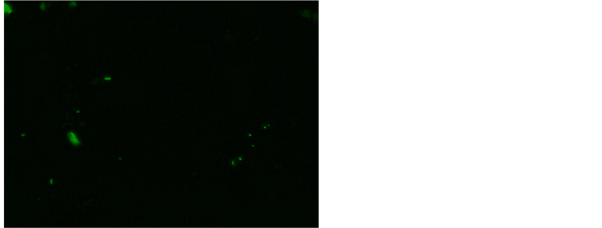

and Rhodamine B [17] . Our study has revealed 56% positive for AFB after fluorescent staining in tissue biopsy and their touch preparations shows 54% positive for AFB after fluorescent staining (Figure 7 and Figure 8). This study shows

Figure 7. AFB in fluorescent stain Auramine O fluorescent stain using Auramine O and Rhodamine B, 200×.

Figure 8. AFB in rod, fragments and beads in and Rhodamine B, 200×.

that both tissue biopsy and touch preparations have all most equivalent AFB and the results of touch preparation for AFB could be seen urgently as compared to the tissue results.